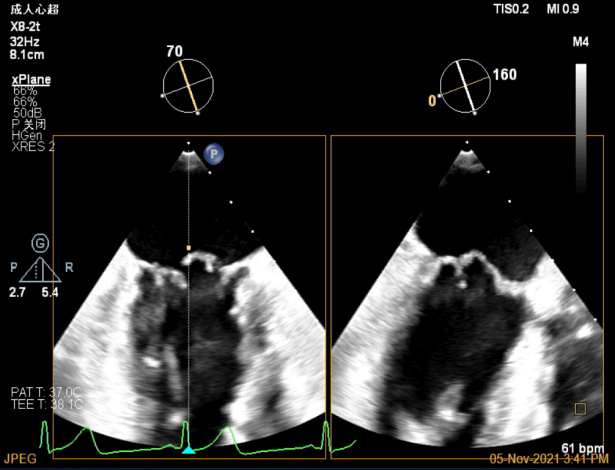

TEE Bicom view:主要脱垂区域为2区

Color-view:返流束主要来源于2区脱垂

A1P1区后叶发育短小,约5.3mm

A2P2区前后叶长度可,为主要脱垂区域,进而制定手术策略: 2区一个长夹子解决脱垂主要病变区域

X-plane:下夹子尝试捕获2区脱垂瓣叶

Gripper,前叶捕获长10.1mm,后叶捕获长度8.9mm